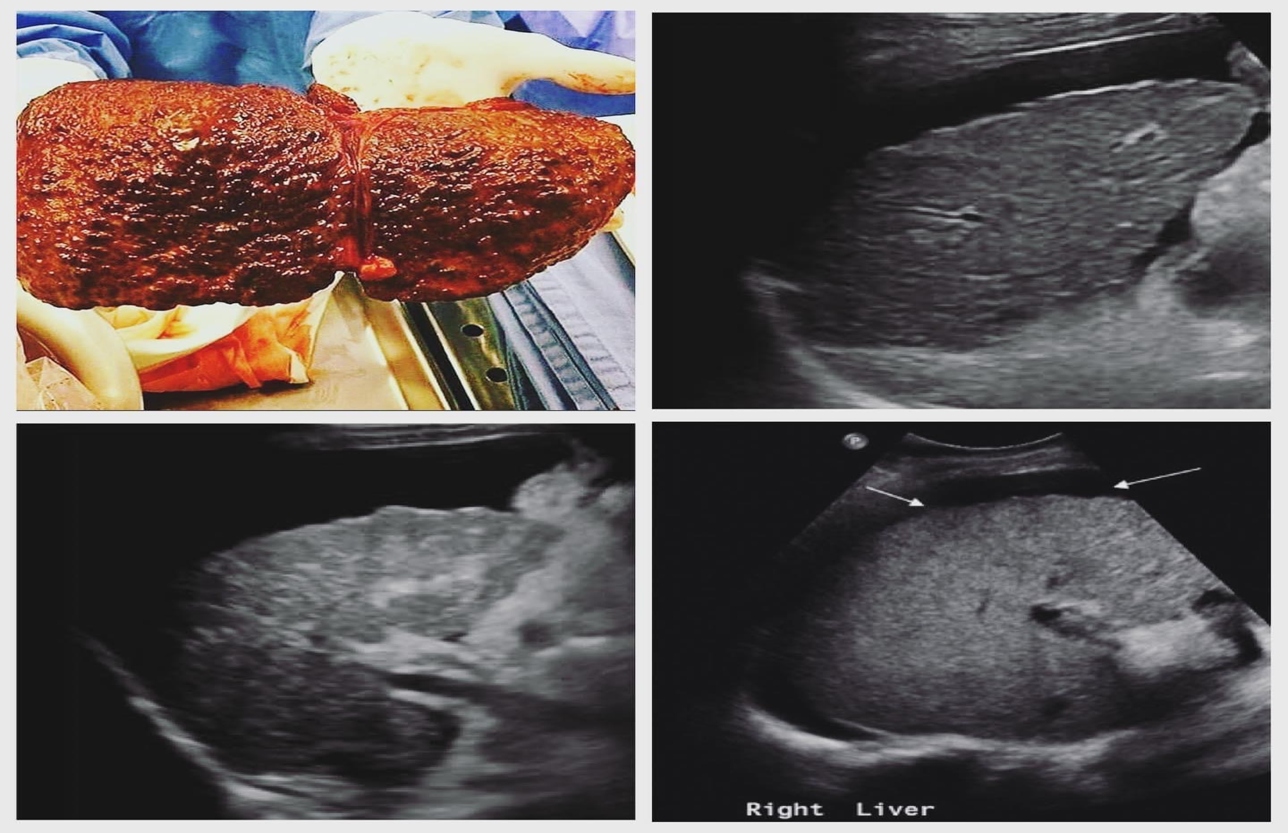

cirrhosis sonographic characteristics

isoechoic regenerative nodules

decreased visualization of vascular structures

cirrhotic liver with ascites

cirrhotic liver

fibrosis and altered architecture of cirrhosis cause a

coarse appearance

inspection of liver surface with what kind of probe demonstrates nodularity

high frequency, linear array